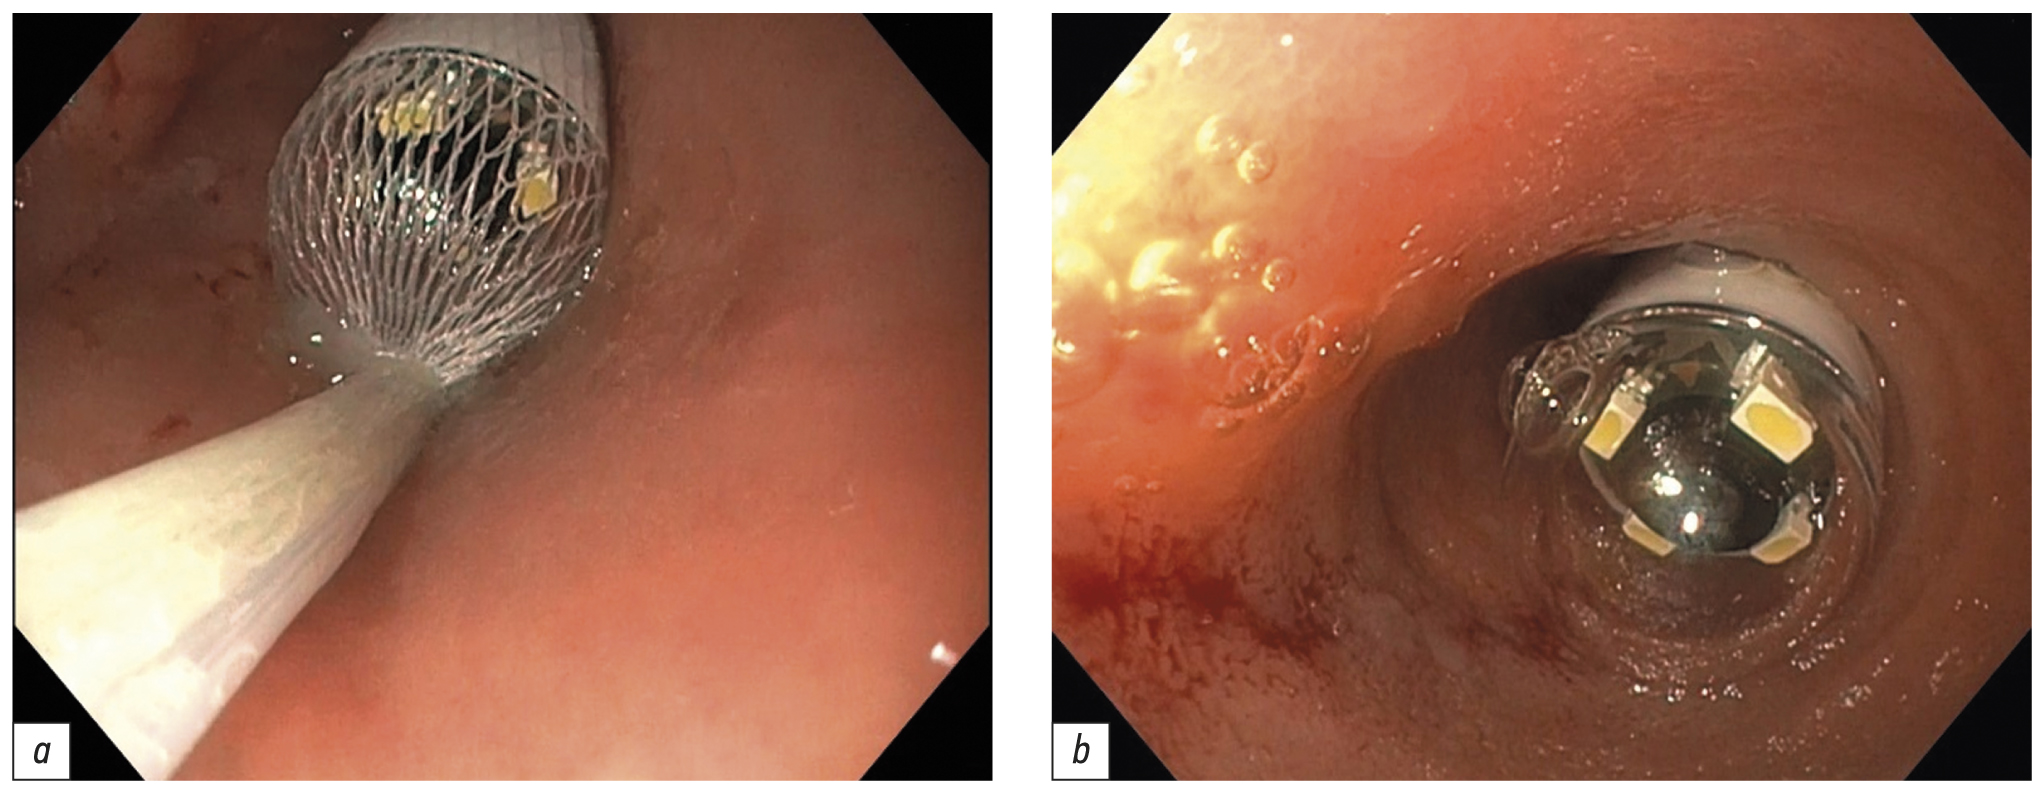

Поскольку в день операции у ребёнка был отмечен очередной эпизод мелены, для исключения поражений Дьелафуа, а также для осмотра тощей кишки на уровне расправленного тонкокишечного инвагината (30–40 см от связки Трейтца) интраоперационным консилиумом принято решение выполнить третье эндоскопическое исследование верхних отделов ЖКТ. В положении ребёнка на левом боку под СО2-инсуффляцией с применением ручного пособия тонкий видеогастроскоп заведён в тощую кишку, где на расстоянии около 40 см от пилорического канала было обнаружено эпителиальное новообразование шаровидной формы размерами 15×17 мм на короткой широкой ножке толщиной около 6 мм (тип 0-Ip по Парижской классификации эпителиальных новообразований) (рис. 6). Поверхность полипа гиперемирована, покрыта единичными округлыми эрозиями с налётом фибрина. Новообразование легко смещалось в просвете кишки при помощи инструментальной пальпации. С целью расширения возможностей инструментария тонкий видеогастроскоп заменён на аппарат стандартного диаметра с рабочим каналом 2,8 мм, который с техническими трудностями, обусловленными малым диаметром просвета ЖКТ у ребёнка, был проведён к новообразованию. Первым этапом с помощью эндоскопического инъектора выполнено введение в подслизистый слой физиологического раствора с индигокарминовым красителем в основание полипа с целью создания гидравлической подушки между слизистой и мышечной оболочками стенки кишки (рис. 7). Отмечен умеренный лифтинг новообразования. Эндоскопической серповидной петлёй Olympus Snare Master 25 мм выполнен захват полиповидного образования в пределах неизменённых тканей и затягивание петли на ножке образования (рис. 8). Выполнено удаление полипа в пределах неизменённых тканей в смешанном режиме коагуляции-резания (электрохирургический блок Olympus) методикой эндоскопической резекции слизистой оболочки. При осмотре после резекции признаков резидуальных тканей новообразования и глубокого повреждения стенки кишки не определялось. Отмечено подтекание крови из ложа удалённого образования. Выполнен гемостаз и сведение краёв дефекта слизистой при помощи трех эндоскопических клипс (рис. 9). Полип извлечён при помощи эндоскопического сачка из просвета ЖКТ и направлен на морфологическое исследование (рис. 10, 11).

Рис. 8. Эпителиальное новообразование захвачено эндоскопической петлёй

Fig. 8. An epithelial lesion is taken by an endoscopic snare

Рис. 9. Пострезекционный дефект слизистой оболочки укрыт тремя эндоскопическими клипсами

Fig. 9. The post resection defect of mucosa is closed by three endoscopic clips